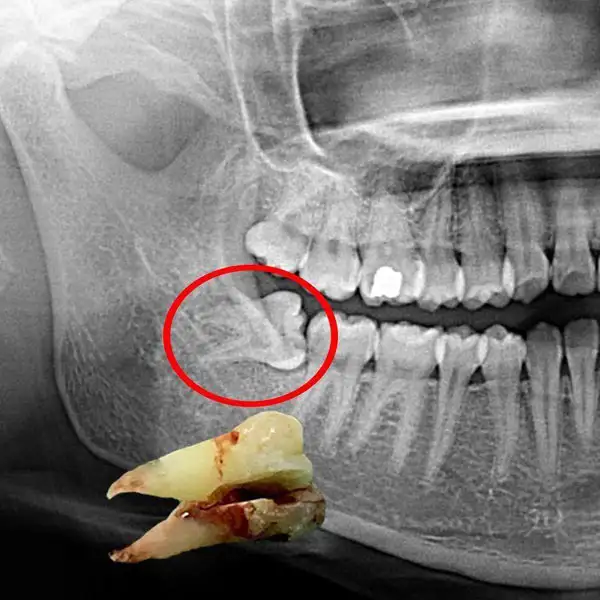

12. Tooth Extraction(Including Wisdom Teeth)

Safe and comfort-focused removal of damaged, decayed, loose, or impacted teeth using modern techniques and advanced anesthesia. Includes simple and surgical extractions such as wisdom tooth removal when required.

Our gentle approach ensures minimal discomfort during the procedure, faster healing, and smooth recovery. Detailed post-extraction care instructions are provided to promote proper healing and prevent complications, helping you return to normal activities quickly and comfortably.